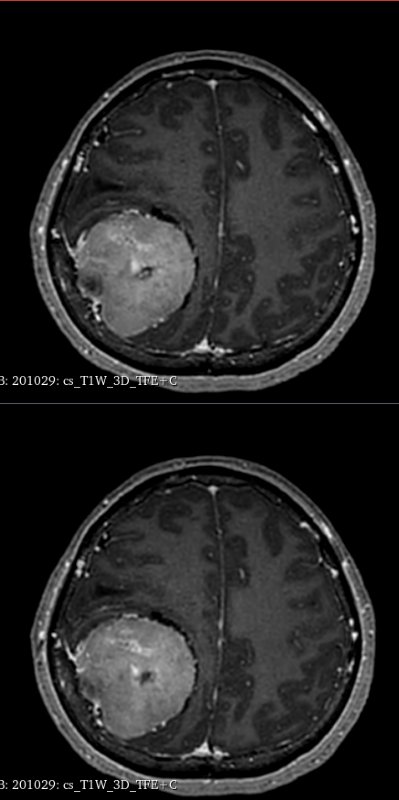

据悉,该患者因“间断头痛4年、加重伴头晕4个月”就诊。头颅MRI检查显示,其右侧顶部巨大占位紧邻中央沟功能区及上矢状窦等重要血管。

术前精准建模:运用3D Slicer软件整合多模态影像数据重建三维模型,清晰呈现肿瘤与周边功能区、血管的空间关系,为手术规划提供精准数字化依据。